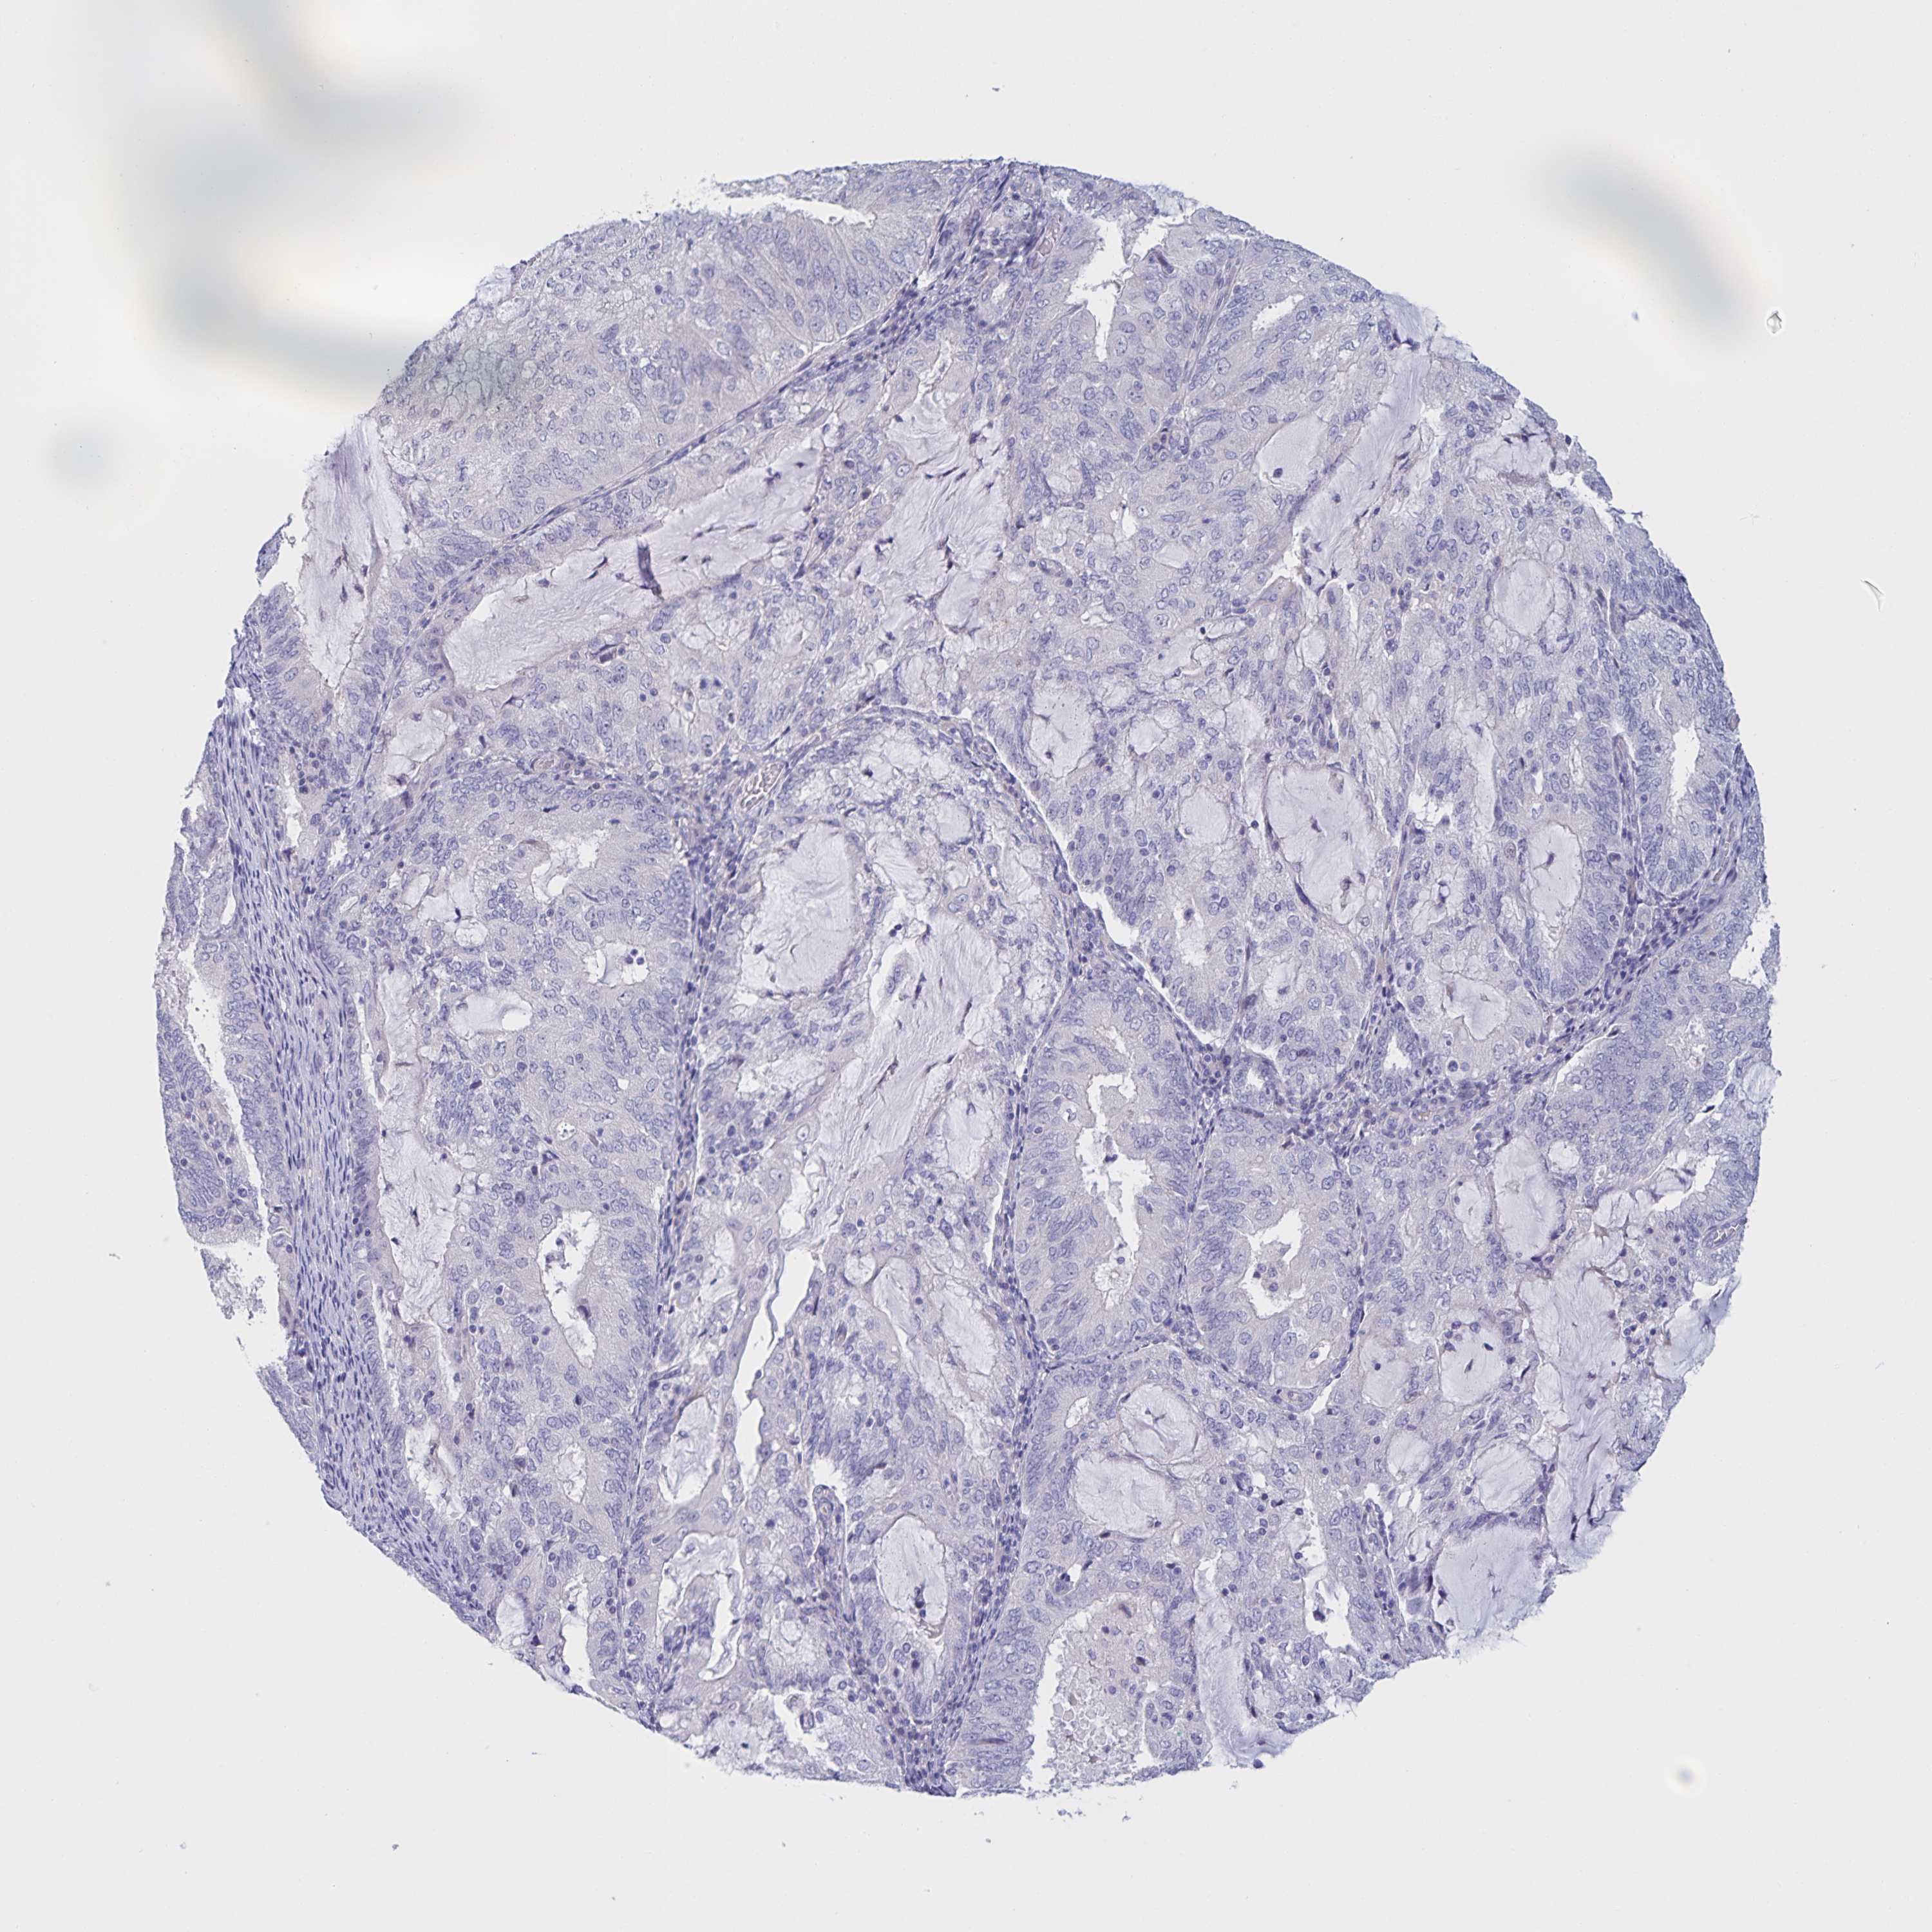

ENDOMETRIAL CANCER - Protein expressioni

A mouse-over function shows sample information and annotation data. Click on an image to view it in a full screen mode. Samples can be filtered based on level of antibody staining by selecting one or several of the following categories: high, medium, low and not detected. The assay and annotation is described here.

Note that samples used for immunohistochemistry by the Human Protein Atlas do not correspond to samples in the TCGA dataset.

Antibody stainingi

Antibody staining in the annotated cell types in the current human tissue is reported as not detected, low, medium, or high, based on conventional immunohistochemistry profiling in selected tissues. This score is based on the combination of the staining intensity and fraction of stained cells.

Each image is clickable and will lead to virtual microscopy that enables deeper exploration of all samples and also displays staining intensity scores, fraction scores and subcellular localization as well as patient and tissue information for each sample.

Antibody HPA036441

Antibody HPA036442

Staining

High

Medium

Low

Not detected

Intensity

Strong

Moderate

Weak

Negative

Quantity

>75%

75%-25%

<25%

None

Location

Nuclear

Cytoplasmic/membranous

Cytoplasmic/membranous,nuclear

Adenocarcinoma, NOS

Adenoma, NOS